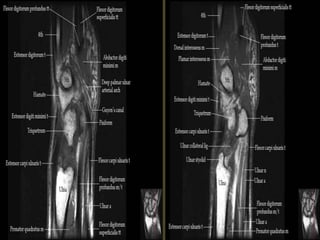

Wrist X-ray Anatomy.

Pronator quadratus.